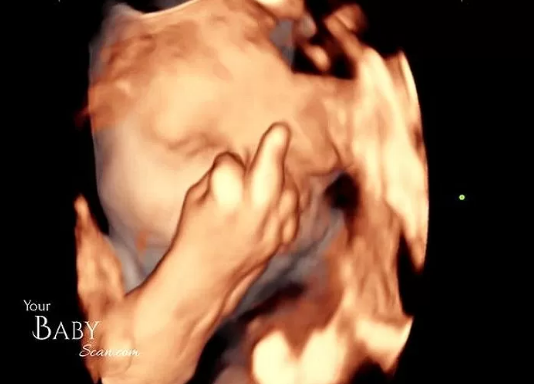

それはイギリスでの出来事。こちらの夫婦に第1子を授かったとのことですが、最近になり夫婦が妊娠30週目のエコー写真を公開しました。そこには胎児の姿がはっきり見えるのですが、胎児が一見変わった仕草を見せているとのこと。なんと、胎児が中指を立てる姿が映し出されていました。

まだ、指が完全に形成されてはいないものの、中指を立てているのが一目瞭然。もしかするとエコー写真を撮られているのに気づいており「早く終わらせろよ…」とアピールしているのかもしれません。これには夫婦も目を疑ってしまいました。